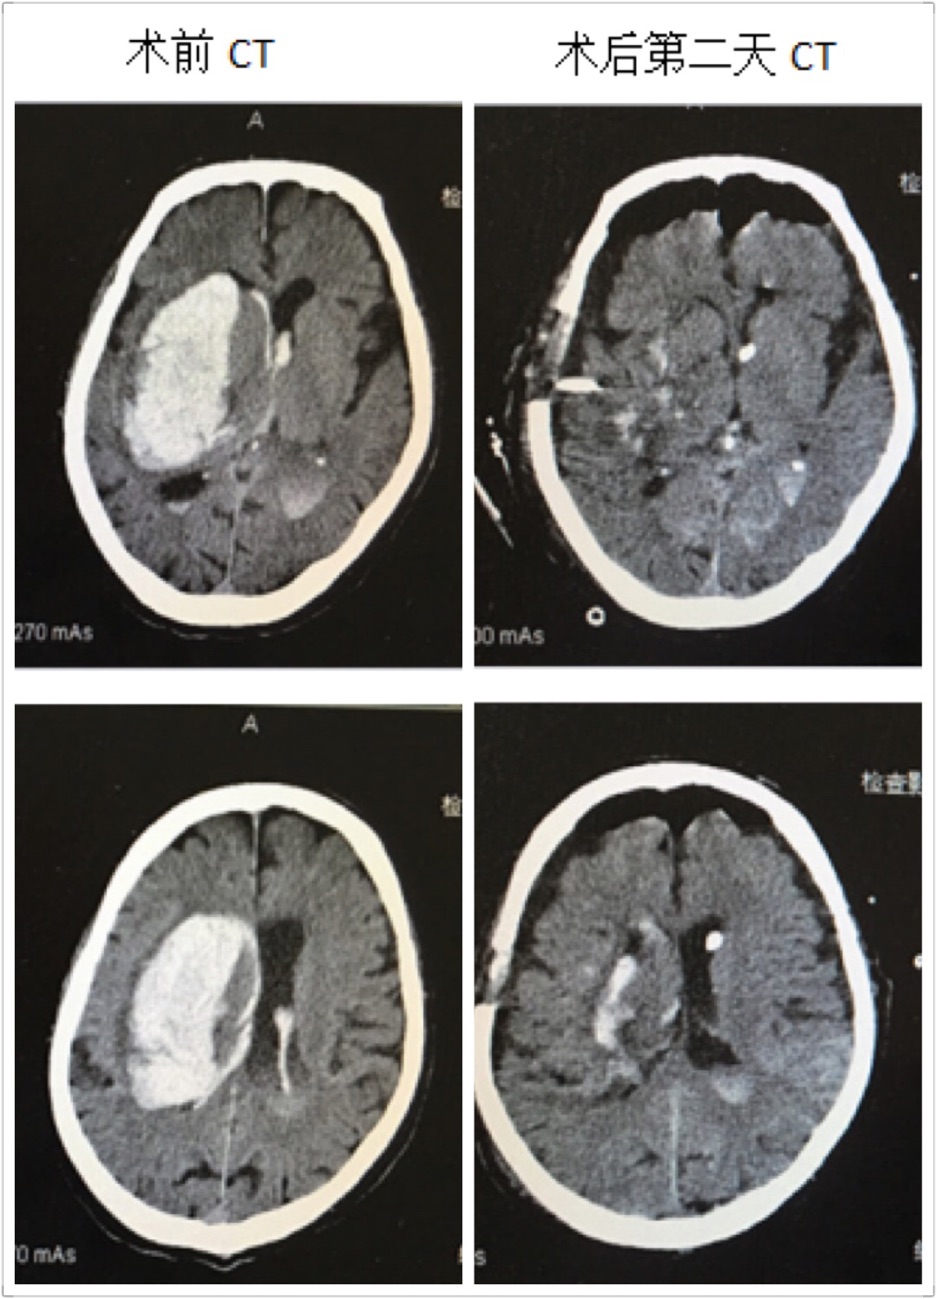

近日,男同视频 神经外科成功救治一名高龄脑出血患者,并顺利康复出院,取得了满意的疗效。这位男性患者86岁,出血量约120ml,入院后处于深昏迷状态,Glasgow评分仅3分,一侧瞳孔散大,颅内高压频繁喷射性呕吐,病情危重,随时有死亡的可能。在这例高龄脑出血患者入院后,男同视频 神经外科王钢副主任医师放弃休息时间,立即组织医疗小组,商讨治疗方案,像这样大量脑出血手术必须手术治疗。在保证血肿清除率及创伤小、出血少的前提下,在我科完成多例神经内镜下血肿清除术的基础下,王钢副主任医师提出:这位高龄患者可以采取小骨窗和神经内镜下清除血肿。

在王钢副主任医师的带领下,和麻醉科曹淑梅主任,杨克副主任一起,经过详细的术前讨论,制定周密的手术方案,急诊在全身麻醉下行脑出血小骨窗及神经内镜下清除血肿。手术十分顺利,手术历时2小时,骨窗大小直径约3cm,术中完全清除血肿,出血极少,术中未输血。术后第2天患者意识状态明显好转,由昏迷转为呼唤睁眼,出院时患者意识已经清醒,并且能够正常交流。